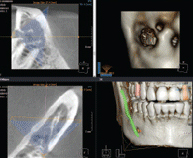

시작부터 다르다!

3차원 정밀진단 시스템

얼굴 골격을 빠짐없이 분석합니다

얼굴 골격의 모든 방향을 빠짐없이 촬영하고

치아와 치조골의 상태 및 잇몸뼈의 양과 길이 등의

전반적인 상태를 정확하게 측정하고 진단하여

한치의 오차 없는 시술로 진료의 안정성을 높힙니다.